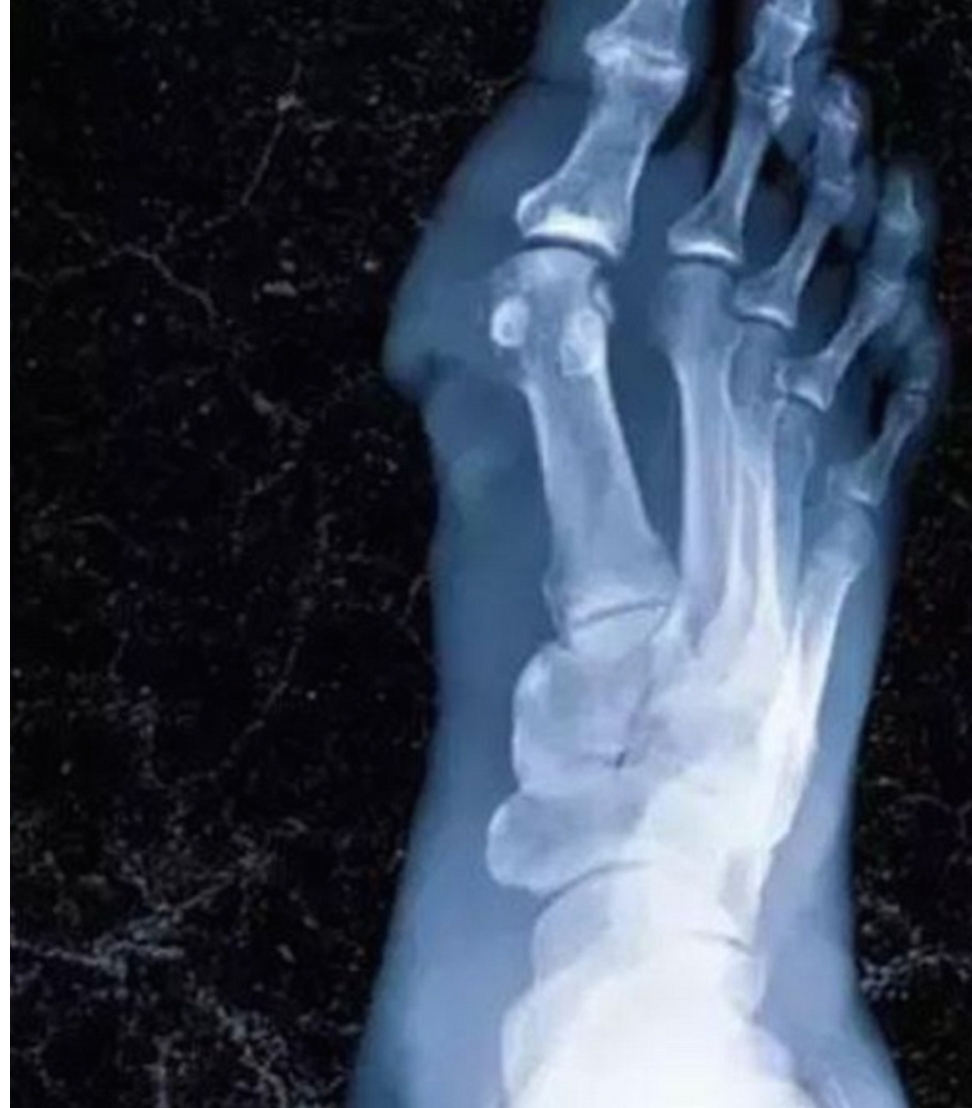

İngiltere’de yayınlanan sağlık dergisi New England Journal of Medicine, bir erkek öğrencinin arkadaşının akşamdan kalan tavuk etli eriştesini yedikten sonra fenalaştığını yazdı. Durumu her dakika kötüleşen öğrencinin hayatını kurtarmak için doktorlar, ellerini ve bacaklarını kesmek zorunda kaldı